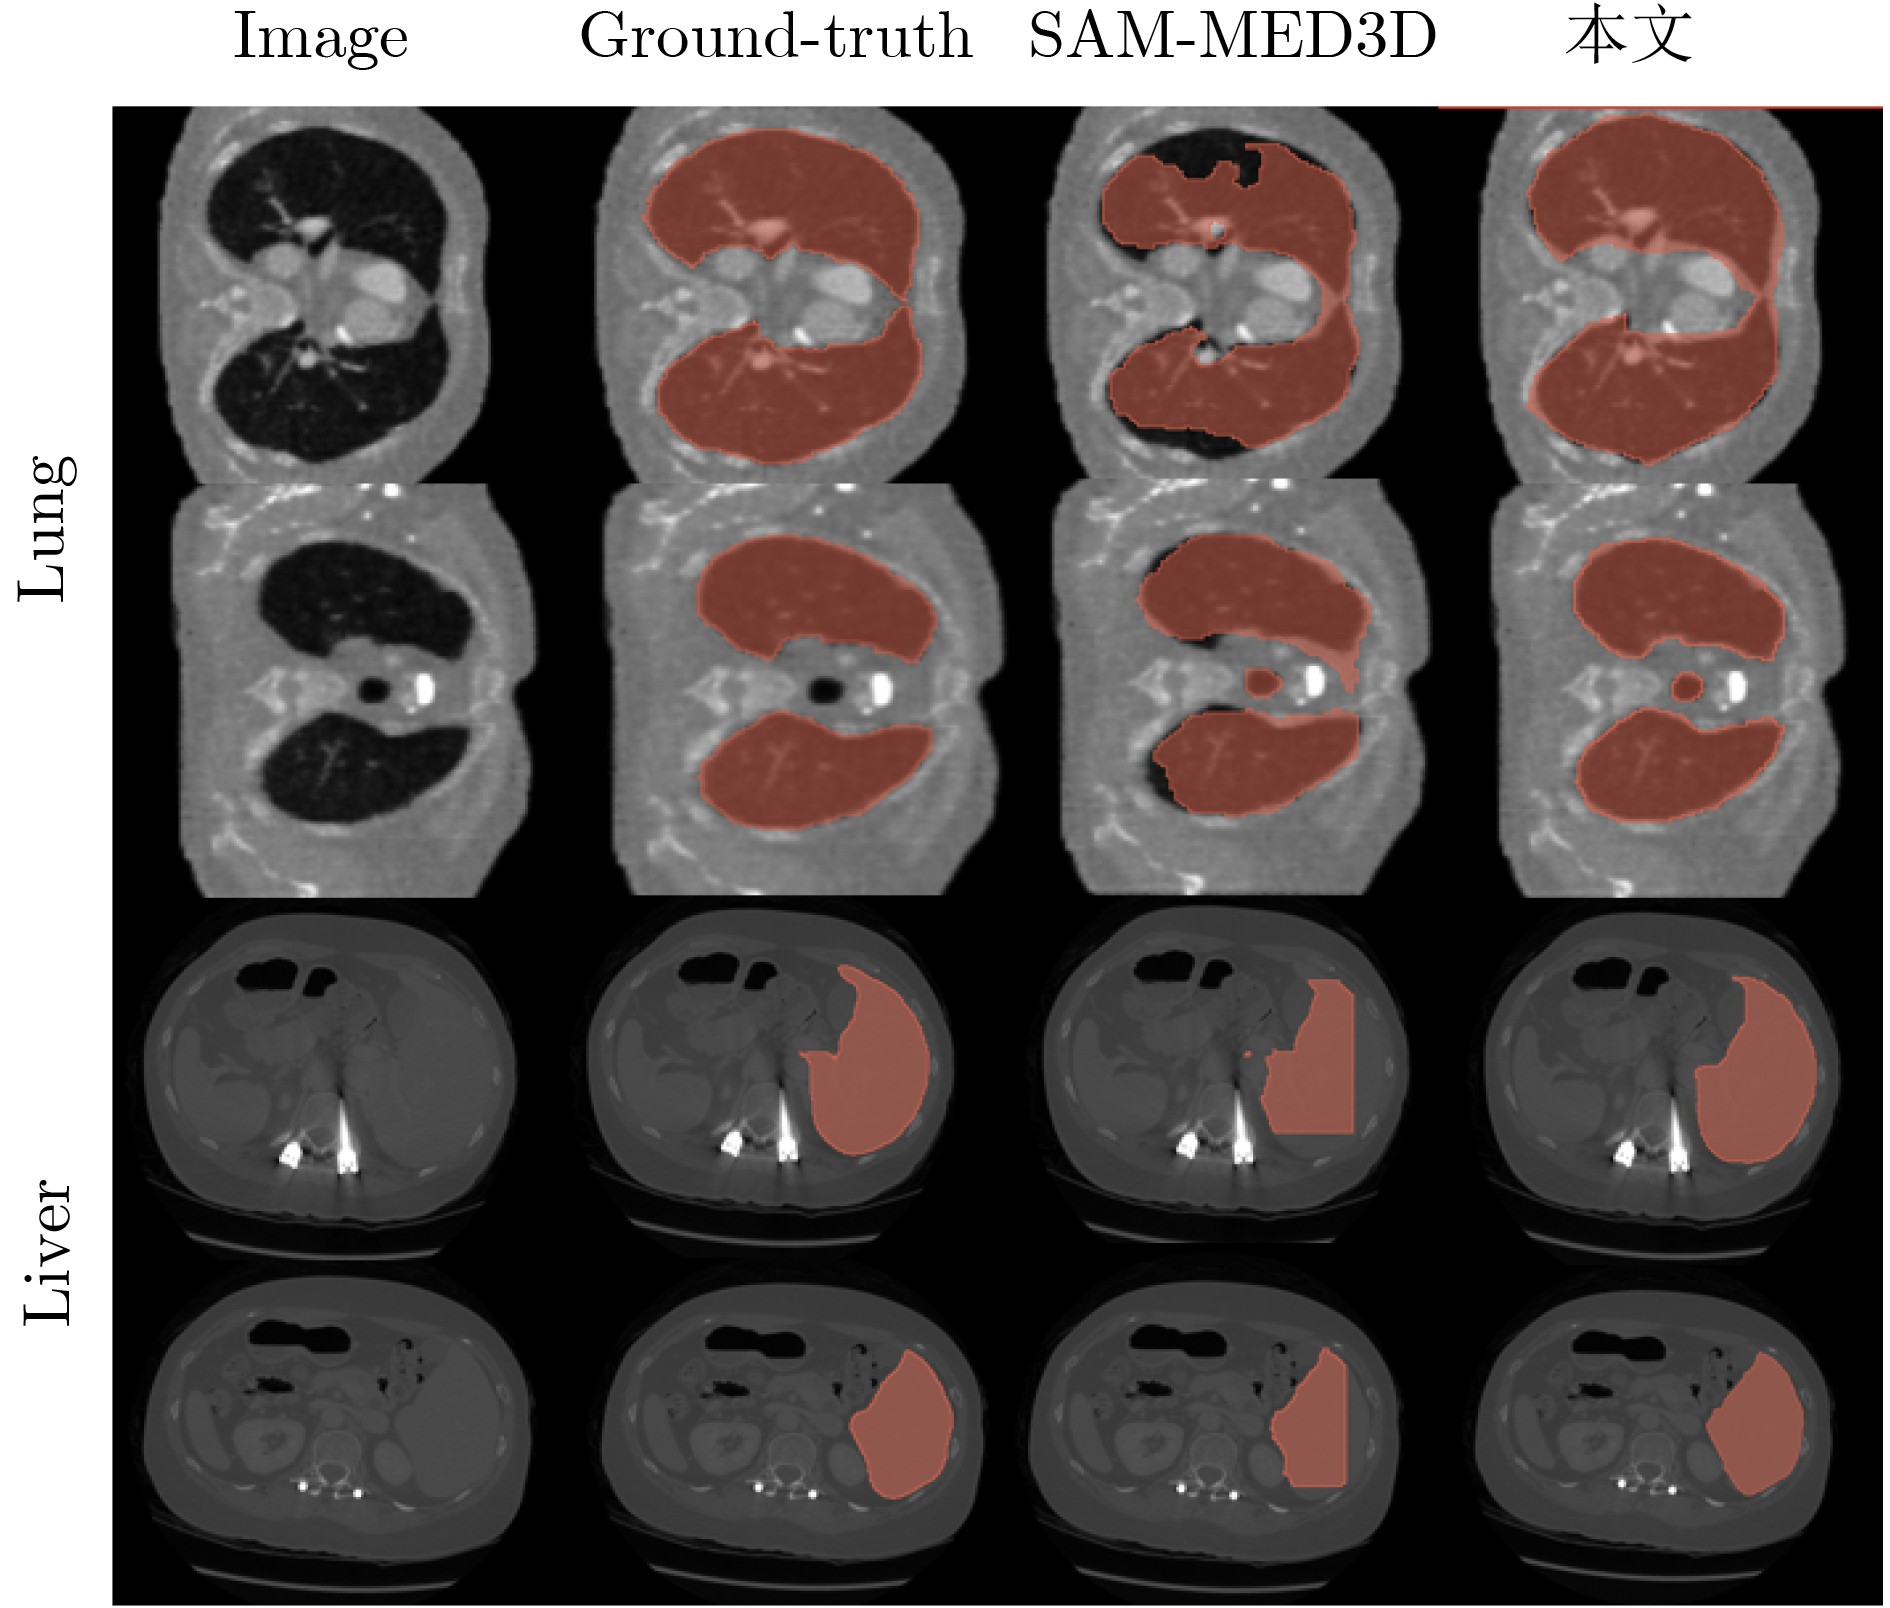

面向稀疏辐射观测的无监督三维医学图像分割方法

俞晓帆, 邹兰兰, 顾文琦, 蔡君, 康彬, 丁康

2026, 48(3): 947-959. doi: 10.11999/JEIT250841

摘要:

神经衰减场是一种具有前景的三维医学图像重建方法,此方法利用稀疏辐射测量实现与完整观察相接近的重构精度。该文提出一种无监督三维医学影像分割方法,将无监督分割与神经衰减场集成为一个端到端的网络架构。具体而言,所提网络架构包括两个阶段:稀疏测量重建和交互式三维图像分割。两个阶段可通过联合学习自适应实现互惠优化。为解决类似肛肠等复杂病灶中边界模糊和区域过度扩展的难题,所提三维分割网络的交互式三维分割阶段设计了密度引导模块,有效利用衰减系数的先验知识,调节密度感知的注意力机制,提升三维分割泛化性能。通过与南京市中医院合作构建的结直肠癌数据集以及两个公开数据集上的大量实验证明所提方法的优越性,例如与基于全辐射观测的SAM-MED3D算法相比,所提网络仅使用14%稀疏观测值,在3个数据集的平均Dice系数提升 2.0%。